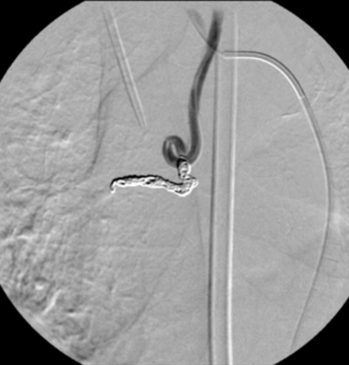

Digitale Subtraktionsangiografie: Nach Spiralembolisation der Bronchialarterie zeigt sich ein kompletter Verschluss des Gefäßes. Die Blutungen (Bluthusten) des Patienten kamen nach dem Eingriff zum Stillstand.